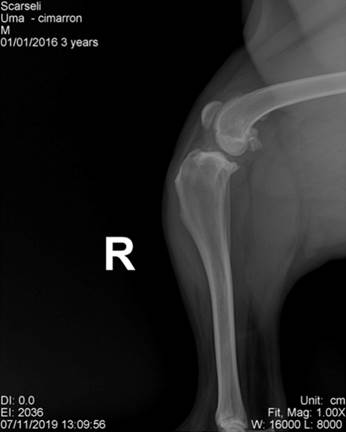

En este trabajo se presenta el reporte de 15 caninos de raza cimarrón uruguayo, diagnosticados e intervenidos quirúrgicamente por RLCA, en una clínica particular, durante los años 2018 y 2019. Durante la anamnesis se registró el tiempo que había transcurrido desde el comienzo de los síntomas hasta el momento de la consulta, así como los tratamientos realizados. El diagnóstico presuntivo de la RLCA, en todos los casos, se realizó mediante el examen clínico traumatológico, incluyendo la prueba de cajón, la prueba de compresión tibial, constatándose la inestabilidad de la articulación. Además, se realizaron radiografías (Figura 2), que mostraron diferentes signos de artrosis de la rodilla. Se evaluó el grado de artrosis mediante la Escala Bioarth. Todos los animales fueron pesados y se evaluó el grado de claudicación en el momento de la primera consulta, según el método descrito por Selmi et al., (2002). La confirmación definitiva de la lesión de la ruptura del LCA se realizó por medio de la artrotomía lateral de la rodilla descrita por Vasseur (2006) (Figura 3:).

Figura 2: Radiografías realizadas a pacientes de la raza cimarrón uruguayo con ruptura de LCA (gentileza del Dr. M. Amilivia)